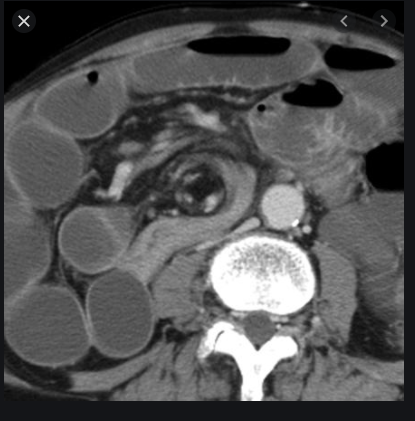

Initial imaging = CT scan abdo-pelvis with contrast

This identifies the site and cause.

CT abdo-pelvis with contrast findings

Dilated sigmoid colon

Whirl sign